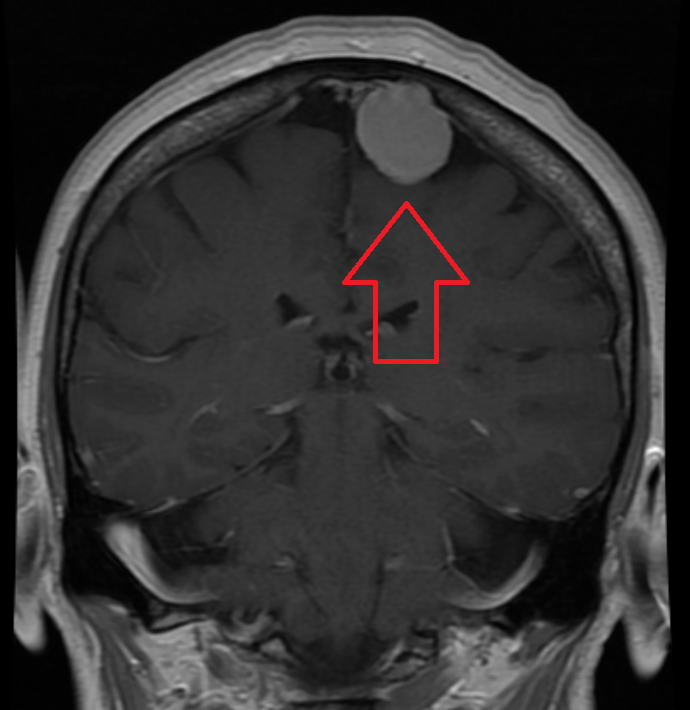

Meningiomas are benign tumors of arachnoid cells.

Meningiomas are the most common benign central nervous system (CNS) tumor in adults.

Meningiomas are more common in females than males.

Meningiomas may cause seizures due to the tumor compressing the cortex without invading it.

Radiology of meningiomas typically show a spherical mass linked to the dura is seen through imaging.

The histology of meningiomas is characterized by a whorled pattern with psammoma bodies.